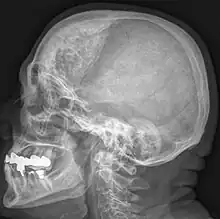

Additional images

Hyperostosis frontalis at CT